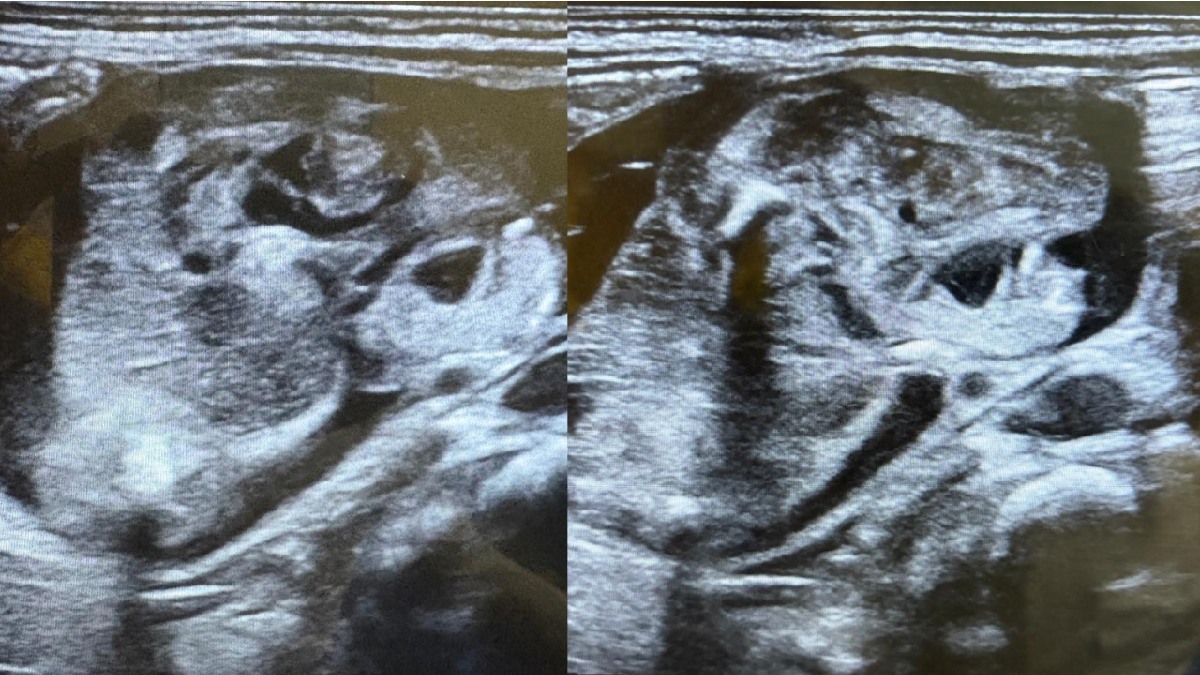

ಕರ್ನಾಟಕ ವೈದ್ಯಕೀಯ ಮಹಾವಿದ್ಯಾಲಯ ಮತ್ತು ಸಂಶೋಧನಾ ಸಂಸ್ಥೆಯ ಆವರಣದಲ್ಲಿ ಮಾತನಾಡಿದ ಅವರು, ಸೆಪ್ಟೆಂಬರ್ 23 ರಂದು ಕುಂದಗೋಳ ತಾಲೂಕಿನ ಪಶುಪತಿಹಾಳ ಗ್ರಾಮದ ಗರ್ಭಿಣಿಯೊಬ್ಬರು ಕರ್ನಾಟಕ ವೈದ್ಯಕೀಯ ಮಹಾವಿದ್ಯಾಲಯ ಮತ್ತು ಸಂಶೋಧನಾ ಸಂಸ್ಥೆಯ ತಾಯಿ ಮತ್ತು ಮಕ್ಕಳ ಆಸ್ಪತ್ರೆಯಲ್ಲಿ ಸಹಜ ಹೆರಿಗೆ ಮೂಲಕ 3.5 ಕೆಜಿ ತೂಕದ ಗಂಡು ಮಗುವಿಗೆ ಜನ್ಮ ನೀಡಿದ್ದರು. ಮಗುವಿನ ದೇಹದಲ್ಲಿ ಎಲುಬಿನ ರೀತಿಯ ಅಂಶಗಳು ಕಂಡು ಬಂದಿವೆ. ಹೃದಯ ಬಡಿತ, ಪುಪ್ಪಸ, ಮೆದುಳು ರೀತಿಯ ಜೀವಂತ ಅಂಶಗಳು ಕಂಡು ಬಂದಿರುವುದಿಲ್ಲ.

ದ್ರವ್ಯ ರಾಶಿಗಳು ರೂಪಾಂತರಗೊಂಡು ಬದಲಾವಣೆ ರೂಪ ಪಡೆದು ಹೀಗಾಗಿತ್ತು. ಹೆರಿಗೆಯಾಗುವವರೆಗೆ ಮಗುವಿನ ಸ್ಕ್ಯಾನ್ ಮಾಡಲಾಗಿದ್ದು, ಮಗುವಿನೊಳಗೆ ಯಾವುದೇ ರೀತಿಯ ಹೆಚ್ಚಿನ ಬೆಳವಣಿಗೆ ಕಂಡು ಬರಲಿಲ್ಲ. ಹೆರಿಗೆ ಬಳಿಕ ಮಗುವಿನ ಸ್ಕ್ಯಾನ್ ಮಾಡಿದಾಗ ಗಡ್ಡೆ ಅದೇ ಜಾಗದಲ್ಲೇ ಇತ್ತು. ಅಕ್ಟೋಬರ್ 7 ರಂದು ಚಿಕ್ಕ ಮಕ್ಕಳ ಶಸ್ತ್ರ ಚಿಕಿತ್ಸಕರಾದ ಡಾ.ರಾಜಶಂಕರ ಅವರು ಮಗುವಿಗೆ ಅತೀ ಸೂಕ್ಷ್ಮ ಶಸ್ತ್ರ ಚಿಕಿತ್ಸೆ ಮಾಡಿದರು. ಪ್ರಸ್ತುತ ಮಗು ಚೇತರಿಸಿಕೊಂಡಿದೆ. ಮುಂದಿನ ದಿನಗಳಲ್ಲಿ ಮಗುವಿನ ಆರೈಕೆಗೆ ಹೆಚ್ಚಿನ ಆದ್ಯತೆ ನೀಡುವಂತೆ ಪೋಷಕರಿಗೆ ತಿಳಿಸಲಾಗಿದೆ. ಕಾಲಕಾಲಕ್ಕೆ ಮಗುವಿನ ಆರೋಗ್ಯ ತಪಾಸಣೆ ಮಾಡಲಾಗುವುದು ಎಂದಿದ್ದಾರೆ.